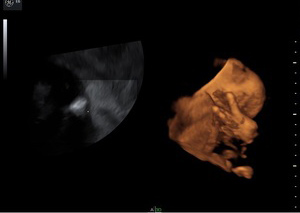

USG 3D / 4D

W nowoczesnych wysokiej klasy aparatach ultrasonograficznych istnieje możliwość przetwarzania danych z badania dwuwymiarowego co umożliwia pokazywanie obrazów trójwymiarowych badanych struktur płodu w czasie rzeczywistym.

Ultrasonografia trójwymiarowa 3D pozwala na uzyskanie statycznych obrazów przestrzennych, które otrzymywane są w procesie obróbki komputerowej danych z badania dwuwymiarowego. Ultrasonografia 4D pozwala na uwidocznienie dynamicznego przestrzennego obrazu.

Ta nowa prezentacja (prezentacja 4D) pochodzi od dodania czwartego wymiaru jakim jest czas. Badanie płodu metodą 4D pozwala nie tylko na obrazowanie przestrzenne płodu ale również pozwala na obserwację ruchów twarzy, obserwację otwierania i zamykania oczu, ruchów języka, ssania palców. Przy korzystnym ułożeniu płodu, w odpowiednim wieku ciążowym ( najlepiej pomiędzy 15. a 35. tygodniem ciąży) możliwa jest diagnostyka szeregu wad rozwojowych płodu. Badanie 4D pozwala też na precyzyjne obrazowanie rozwoju płodu i umożliwia podejrzenie wyglądu dziecka, którego wygląd jest niemal identyczny z jego rzeczywistym wyglądem.

Zastosowanie techniki 3D i 4D ma szczególne zastosowanie w położnictwie. Umożliwiają precyzyjną ocenę narządów wewnętrznych płodu, np. serca, mózgowia, kręgosłupa, twarzy oraz w sposób istotny pozwalają na zwiększenie wykrywalności wad budowy płodu .